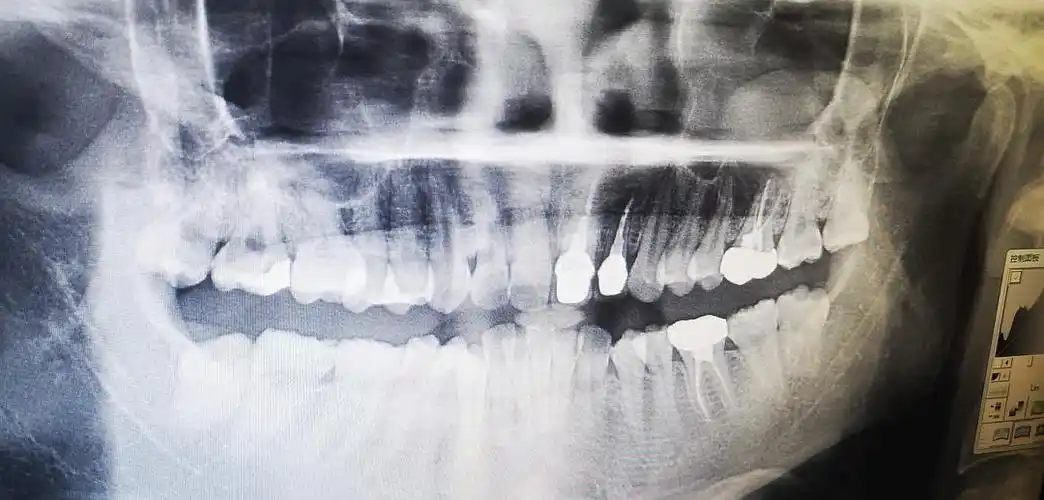

可以帮忙看看我的牙片吗

医生您好这是我的牙片请从您的专业经验来看我的上下牙主要是哪些问题

给大家看看我的牙片